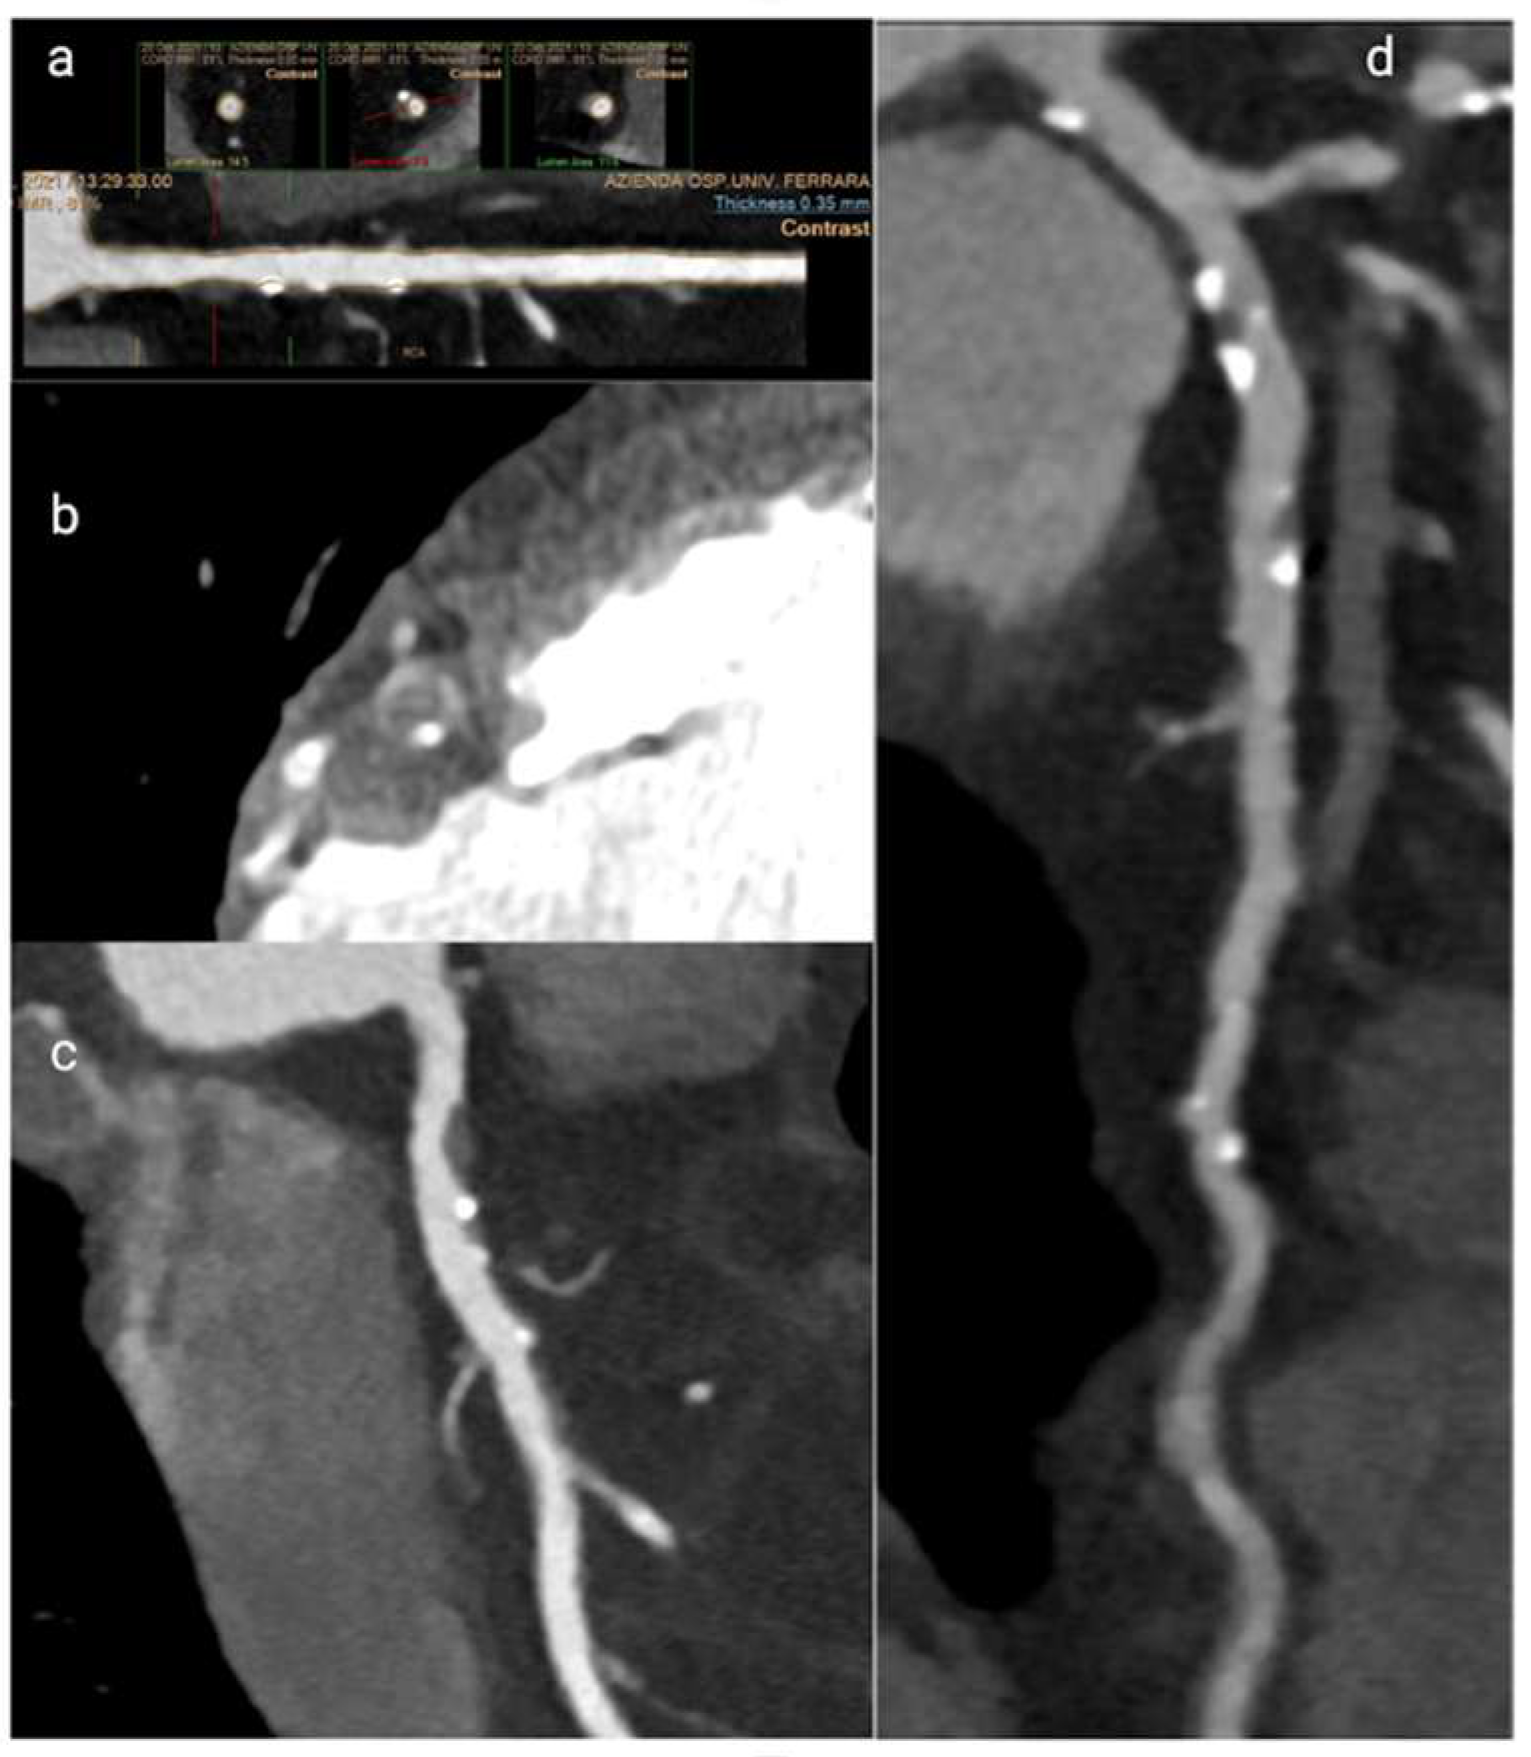

- Leschka, S.; Koepfli, P.; Husmann, L.; Plass, A.; Vachenauer, R.; Gaemperli, O.; Schepis, T.; Genoni, M.; Marincek, B.; Eberli, F.R.; et al. Myocardial Bridging at CT Angiography. Radiology 2008, 246, 754–762. [Google Scholar] [CrossRef]

- Brolin, E.B.; Brismar, T.B.; Collste, O.; Y-Hassan, S.; Henareh, L.; Tornvall, P.; Cederlund, K. Myocardial Bridging in MINOCA. Am. J. Cardiol. 2015, 116, 1833–1839. [Google Scholar] [CrossRef][Green Version]